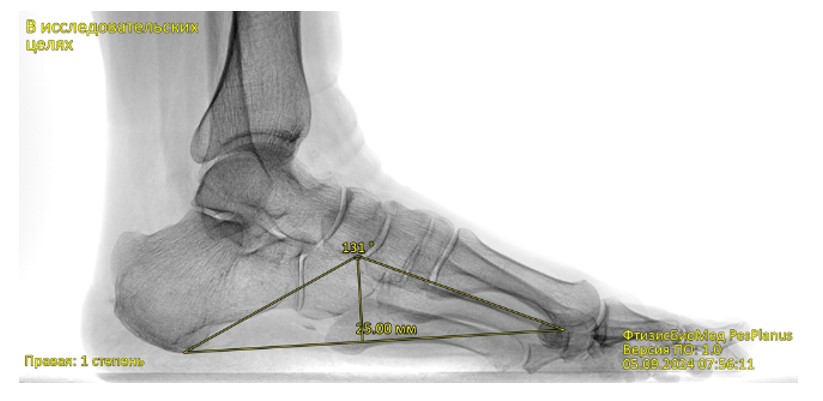

Chương trình phân tích tự động ảnh ‘X-quang bàn chân’ phát hiện bàn chân bẹt dọc và bẹt ngang

FtizisBioMed PesPlanus được phát triển nhằm phân tích tự động hình ảnh X-quang kỹ thuật số của bàn chân, hỗ trợ bác sĩ trong việc:

Phát hiện sớm các dấu hiệu bàn chân bẹt dọc và bẹt ngang;

Giải pháp công nghệ

Chương trình ứng dụng trí tuệ nhân tạo y tế (Medical AI) và các mô hình học máy tiên tiến để phân tích hình ảnh X-quang bàn chân. Hệ thống được huấn luyện trên tập dữ liệu lớn đã được gán nhãn bởi các chuyên gia đầu ngành, đảm bảo độ tin cậy và khả năng tái lập kết quả cao.

Tự động phát hiện và nhận diện nhiều dấu hiệu bệnh lý hình thái bàn chân, hỗ trợ tự động hóa bước đọc phim ban đầu.

Nhờ quá trình huấn luyện học máy trên dữ liệu chất lượng cao, chương trình đạt được các chỉ số hiệu năng cao, đáp ứng yêu cầu ứng dụng trong môi trường lâm sàng và sàng lọc quy mô lớn.